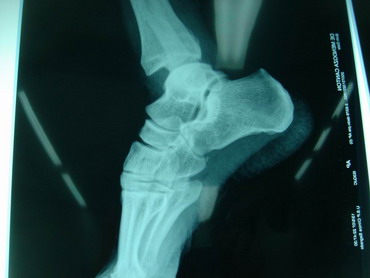

14 - 5 - 07 El torero se interviene hoy a la 12,30 horas en la Clínica Sagrado Corazón de Sevilla. Se confirma diagnóstico provisional hecho en la enfermería de la plaza de Osuna. Fractura de tibia y peroné. Con las siguientes connotaciones: La fractura de peroné es completa y compleja consta de 4 fragmentos diferentes con desplazamiento de los mismos. es decir una fractura conminuta. La tibia presenta fractura maleolar con desplazamiento y además con respecto al tobillo existe una subluxación de la articulación debida a la rotura o explosión de la cápsula articular con desflecamiento de la misma. En resumen un cuadro complejo de tobillo inestable que precisa intervención quirúrgica inmediata. Se estabilizan las fracturas, se sutura la cápsula anterior, se reduce la subuxación, se administran factores de crecimiento y se inmoviliza extremidad. Pronóstico grave. Se estima un tiempo de recuperación de 90 días. Dr. Minguet. Dr. Periañez. Dr. Vaz. Dr. Morales |